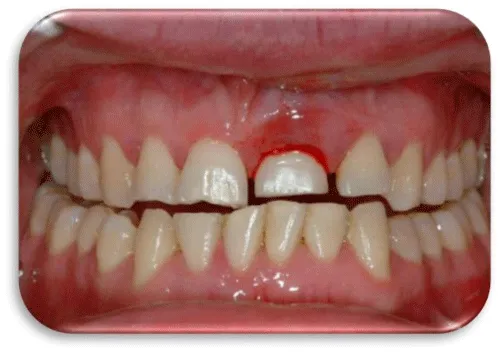

Peri-implant diseases are classified into two categories: - Peri-implant mucositis, which would be described as a bacterial-induced, inflammatory process that involves soft tissue. Clinically, redness of the gingiva is noticeable, it is oedematous and bleeding occurs during the probing.

- Peri-implantitis characterized by progressive, inflammatory destruction of the alveolar bone around the implant. Deepening of the gingival sulcus occurs, the purulent and bloody contents are drained during the projection [10,11] (Figures 2,3).

In peri-implant mucositis, the marginal gingiva in lightly bleeding bleeds. Gingiva is hyperemic and oedematous. The patient feels discomfort, mastication of food also leads to bleeding (Figure 4) [16].